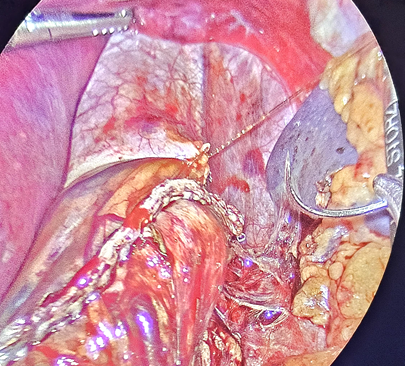

The SG is then performed by dividing the gastroepiploic omentum from the greater curvature with an ultrasonic scalpel (Sonicision TM Medtronic) starting 6cm from the pyloric vein to the angle of His, until the left crura of the hiatus was observed. The gastro-splenic and gastro-phrenic ligaments are also divided. The fat pad that covers the His angle is excised with the same instrument. A 36Fr bougie is passed to the stomach to construct the gastric tube using five or six cartridges of the Endo GIA 60 tristaple (CovidienTM) to divide the greater curvature. The proximal gastric plication is then performed to create an internal antireflux valve in the upper 3cm on the lateral side of the gastric tube by using a grasper to invaginate 2cm of the gastric wall of the stomach with sero-muscular stitches of a running suture of 2-0, 45cm spiral Monocryl (Stratafix Ethicon ®), and then continue the suture to reinforce the rest of the staple line (Figure 1-3). This invagination reduces the gastric bulb that is frequently observed at the proximal staple line and serves to decrease the gastric lumen at this point; serving as an internal anti-reflux valve.

Figure 3 Running suture with 2-0 sero-muscular inverted Stitches to reinforce the rest of the stapled line.